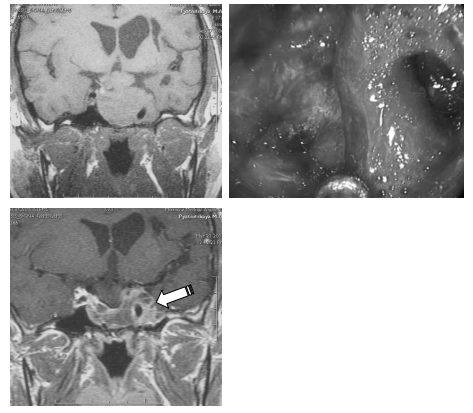

Нередко вторичные узлы опухоли отходят не от супраселлярной части, а от раздутого аденомой кавернозного синуса. В этих случаях удаление вторичных узлов становится возможным лишь после более или менее радикального удаления аденомы из полости кавернозного синуса (рис. 10).

Рис. 10. Пример удаления эндо-супра-латероселлярной аденомы: А — МРТ до операции; от верхней стенки синуса отходит вторичный узел опухоли; Б — МРТ после операции; явных остатков опухоли не определяется

На рис. 14 представлен другой пример частичного удаления большой эндо-супра-латероселлярной аденомы гипофиза. По данным контрольной КТ на вторые сутки после операции, можно лишь сказать, что хирург удалял опухоль из синуса, однако очевидно, что удалена была не вся аденома, что также подтверждается субъективным мнением хирурга, отраженным в протоколе операции — плотные фрагменты аденомы, фиксированные к капсуле и стенкам сонной артерии, не удалялись.

Рис. 13. Пример субтотального (?) удаления большой эндо-супра-латероселлярной аденомы гипофиза: А, Б, В — МРТ до операции; Г, Д — КТ в первые сутки после операции

Рис. 14. Пример частичного (?) удаления большой эндо-супра-латероселлярной аденомы гипофиза: А — МРТ до операции; Б — КТ на вторые сутки после операции — в полости вторичного узла кровь, гемостатические материалы, остатки опухоли; оценить радикальность проведенной операции по данным КТ сложно

По данным контрольной КТ, произведенной не сразу после операции, достаточно сложно судить о радикальности проведенной операции — в образовавшейся полости скапливается кровь, кровью пропитываются гемостатические материалы, имбибируются остатки опухоли (рис. 14, Б).